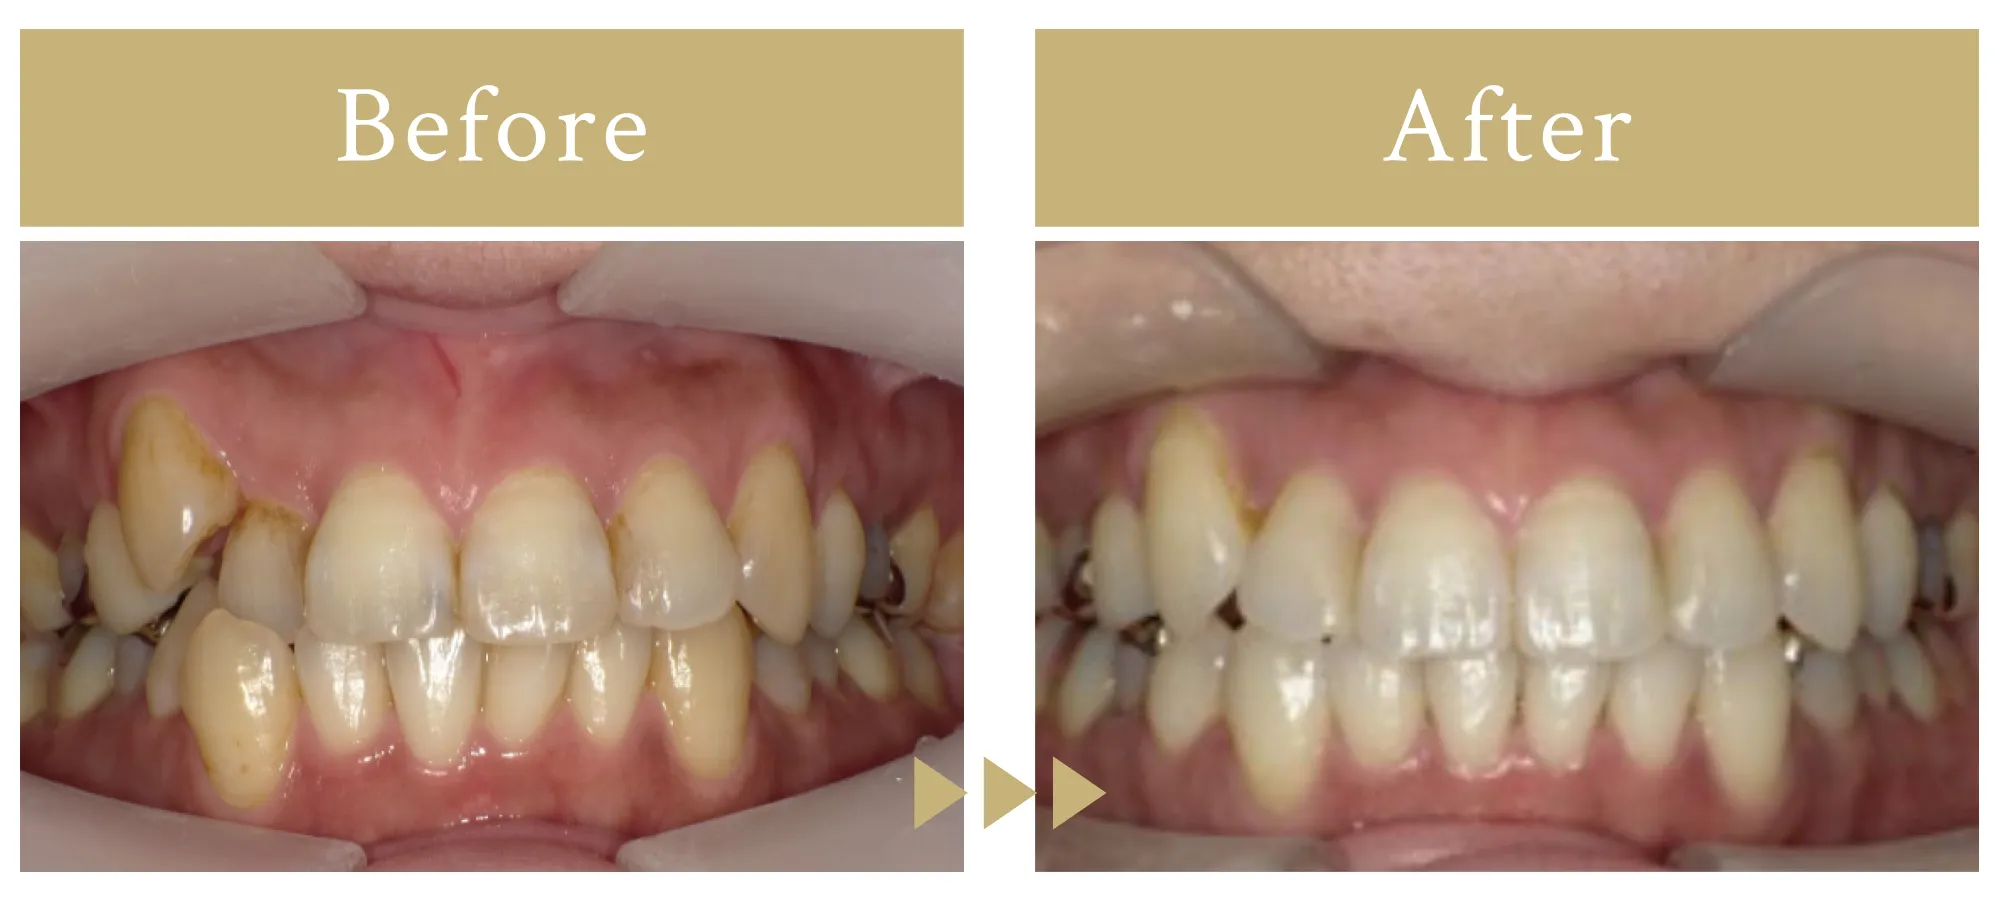

抜歯なしのインビザライン矯正

患者様は抜歯しないで歯並び矯正が出来るかという相談だったので、当院では、精密診断して抜歯しないでできる歯の状態かどうかを調べてインビザラインをおすすめしました。

91.3万/8ヶ月

矯正終了後、後戻りが起きないようにする目的でリテーナーを装着する必要があります。

女性

患者様は抜歯しないで歯並び矯正が出来るかという相談だったので、当院では、精密診断して抜歯しないでできる歯の状態かどうかを調べてインビザラインをおすすめしました。

91.3万/8ヶ月

矯正終了後、後戻りが起きないようにする目的でリテーナーを装着する必要があります。